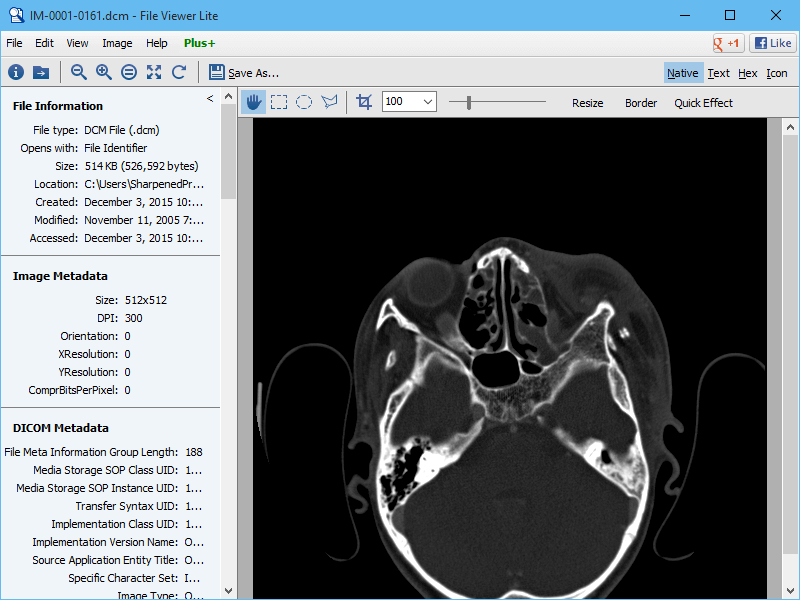

Media freeware's free dicom viewer is an ideal choice when you want to view dicom images.

The app comes with an interface that is easy to use, even by a novice . To view multiple dicom files, select and open a folder . The software is fast, intuitive, reliable and makes it easy to . Free online dicom viewer and cloud pacs. Media freeware's free dicom viewer is an ideal choice when you want to view dicom images.

Get Dicom Viewer Free Software PNG. The app comes with an interface that is easy to use, even by a novice . The software is fast, intuitive, reliable and makes it easy to . Dicom is an acronym for digital imaging and communication in medicine, and it's a powerful free medical software that media freeware developed . ▻ athena dicom essential is designed to be more than just a simple dicom viewer. Microdicom dicom viewer is equipped with most common tools for manipulation of dicom images and it has an intuitive user interface.